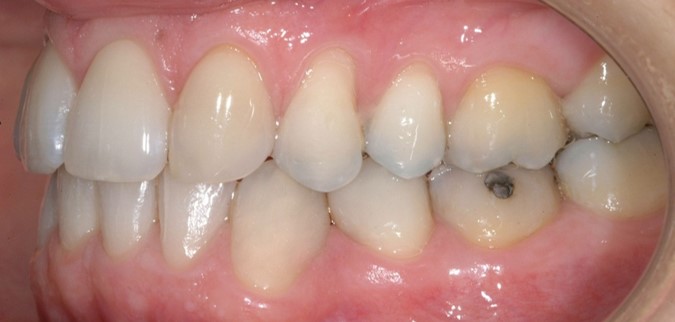

Una paziente di sesso femminile, 38 anni, già trattata ortodonticamente presso altra sede con apparecchiatura fissa a entrambe le arcate in età adolescenziale senza successiva applicazione di alcuna contenzione, si presenta alla nostra attenzione perché insoddisfatta dell’estetica del sorriso; richiede una valutazione per un trattamento ortodontico con apparecchiatura fissa linguale per la presenza di affollamento dentale a entrambe le arcate e difficoltà a mantenere una adeguata igiene orale; si riscontrano agenesia di entrambi gli incisivi laterali superiori (1.2 e 2.2) e del secondo premolare inferiore destro (4.5). Presentiamo la risoluzione del caso mediante trattamento ortodontico estrattivo a entrambe le arcate, eseguito con apparecchiatura linguale invisibile 2D e meccanica asimmetrica e seguito a medio termine da riabilitazione implanto-protesica e contenzione fissa.

Per formulare corretta diagnosi e piano di cura, lo studio del caso ha previsto la raccolta di documentazione completa standard, ovvero fotografie del viso e intraorali (Figure 1a-e), radiografia panoramica e teleradiografia del cranio in proiezione laterale (Figure 2a-b) per la relativa analisi cefalometrica e modelli di studio.

La valutazione clinica e gli esami effettuati confermano la presenza di agenesia degli incisivi laterali superiori (1.2 e 2.2) e del secondo premolare inferiore destro (4.5).

L’analisi ortodontica e la valutazione parodontale, con particolare riferimento alla posizione della radice del canino superiore destro (1.3), distoinclinata e trasposta alla radice del primo premolare (1.4) come evidente dalla radiografia panoramica e dalle immagini intraorali, ci hanno guidati nella programmazione di un trattamento estrattivo asimmetrico a entrambe le arcate.